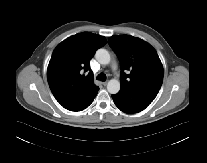

CT Scan showing a large cancer in the right kidney with invasion into the renal kidney vein and inferior vena cava

CT Scan showing kidney cancer metastasis to the mediastinal lymph nodes